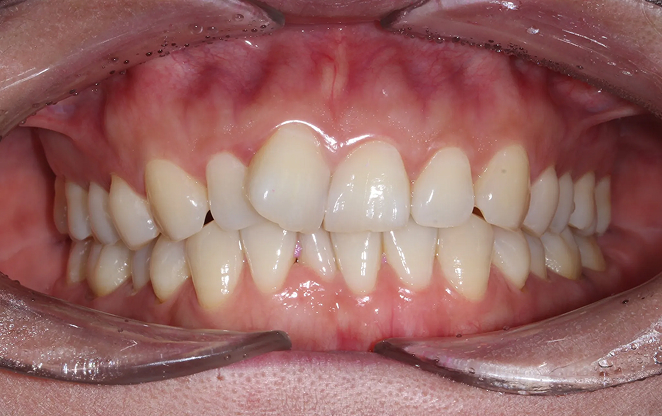

Before

After